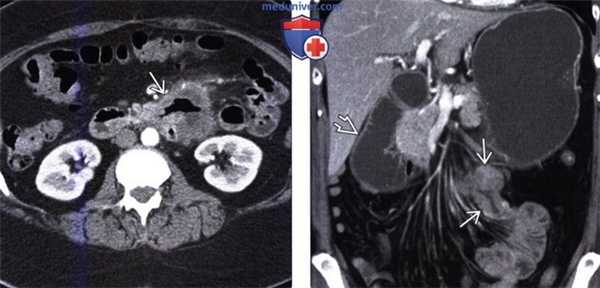

Лимфома тонкой кишки у мужчины 70 лет.

(а) При КТ с контрастированием визуализируется циркулярная инфильтрирующая опухоль (стрелки) тонкой кишки с аневризматическим расширением вовлеченного просвета.

(б) При ПЭТ-КТ с использованием 18F-FDG выявляется гиперметаболизм лимфомы тонкой кишки (стрелки). Множественные лимфомы тонкой кишки у мужчины 34 лет.

При КТ в коронарной проекции визуализируется циркулярное утолщение стенки (белые стрелки) в области терминального отдела подвздошной кишки с легким, гомогенным накоплением контрастного вещества.

Отмечается аневризматическое расширение вовлеченного сегмента. Выявляются множественные увеличенные лимфатические узлы (белые указатели) брыжейки.

Спаянные лимфатические узлы пережимают лимфатический сосуд (черные указатели) с образованием «симптома сэндвича».

Также сегментарное утолщение стенки отмечается в тощей кишке (черная стрелка). Визуализируется кишечно-кишечная инвагинация.

Было установлено, что опухоли тощей кишки и терминального отдела подвздошной кишки представляют собой лимфому Беркитта. Лимфома тонкой кишки (диффузная крупноклеточная В-клеточная лимфома) у мужчины 66 лет.

(а) На прицельной рентгенограмме при пассаже бария по тонкой кишке выявляется неравномерное утолщение складок кишки (стрелки).

(б) При КТ с контрастированием в коронарной проекции визуализируется сегментарное циркулярное утолщение стенки (стрелки) вовлеченного сегмента тонкой кишки с гомогенным накоплением контрастного вещества.

Лимфома тонкой кишкиа характеризуется большим разнообразием рентгенологических проявлений. Чаще всего она представляет собой циркулярно инфильтрирующую опухоль, которая может сопровождаться аневризматической дилатацией пораженного просвета. При КТ с контрастированием отмечается циркулярное утолщение стенки с легким или умеренным гомогенным накоплением контрастного вещества.

Аневризматическая дилатация тонкой кишки возникает в результате деструкции вегетативных нервных сплетений собственной пластинки, приводящей к снижению тонуса гладкой мускулатуры. Необходима дифференциальная диагностика с инфильтративным типом аденокарциномы, при котором аневризматическое расширение кишки не отмечается. При лимфоме тонкой кишки обычно отсутствует десмопластическая реакция. К другим вариантам лимфомы тонкой кишки относятся единичные или множественные узловые или полиповидные образования.

(Слева) На аксиальной КТ с контрастным усилением у мужчины 58 лет с известной злокачественной меланомой визуализируется одно из нескольких мягкотканных образований в брыжейке. Метастазы, вероятно, стали причиной инвагинации.

(Справа) На аксиальной КТ с контрастом у этого же пациента, выполненной спустя пять месяцев после обнаружения инвагинации длинного сегмента, определяется один из метастазов в стенке кишечника, ставший ее причиной. (Слева) На аксиальной КТ с контрастным усилением у мужчины 46 лет с известной неходжкинской лимфомой определяется распространенное мультифокальное утолщение стенки кишечника и аневризматическая дилятация просвета подвздошной кишки.

(Справа) На корональной КТ с контрастным усилением у этого же пациента определяется распространенная лимфаденопатия брыжейки, а также обрастание брыжеечных сосудов, но без обструкции кишечника либо сосудов. Также визуализируются множественные очаги лимфомы.